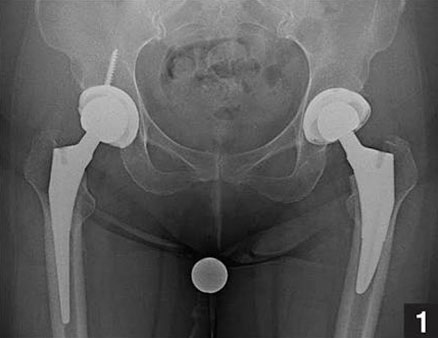

I had arthritis of both my hips due to

a condition called avascular necrosis. I used to walk with severe limp, and could not sit properly due

to the condition of my hips. Dr. Anuj Agrawal did uncemented hip replacements for both my hips, at an

interval of 6 weeks. I could walk without support just 2 weeks after the second surgery and could even

ride a scooter at 1 month. I have become completely painless now, and am quite happy by the outcome of

the surgery. I would highly recommend Dr. Anuj Agrawal for hip replacements.

Total hip replacement (THR) involves replacement of both the ball (femur) and socket (acetabulum) of the hip joint. The femoral component is a modular one, consisting of a stem (made of metal such as cobalt-chrome or titanium) and head-neck (made of metal or ceramic). The acetabular component can be made of ceramic, metal or plastic (UHMWPE). The components are fixed to the parent bone by either bone cement (cemented hips) or by natural bone ingrowth/ongrowth over special porous or roughened surfaces (uncemented hips). Uncemented hips are costlier than cemented hips, and are supposed to have longer survivorship.